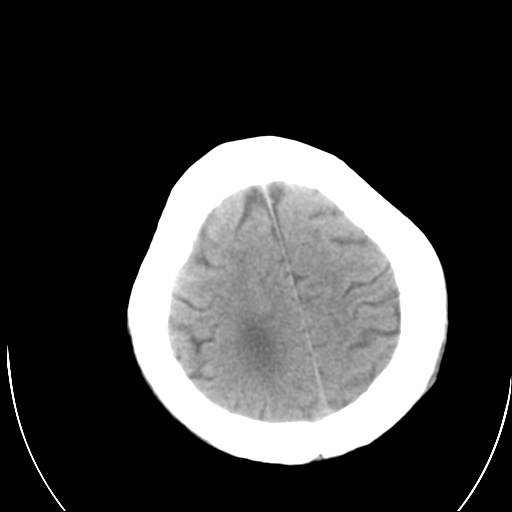

以下是引用泪洒红尘在2009-3-23 19:53:00的发言:[br]第四脑室以上脑室明显扩大,脑沟脑裂无明显增宽加深征象,符合交通性脑积水ct表现。

以下是引用xulianj在2009-3-23 20:31:00的发言:[br]右侧侧脑室扩大,中线结构左移,考虑梗阻性脑积水,建议mri检查。